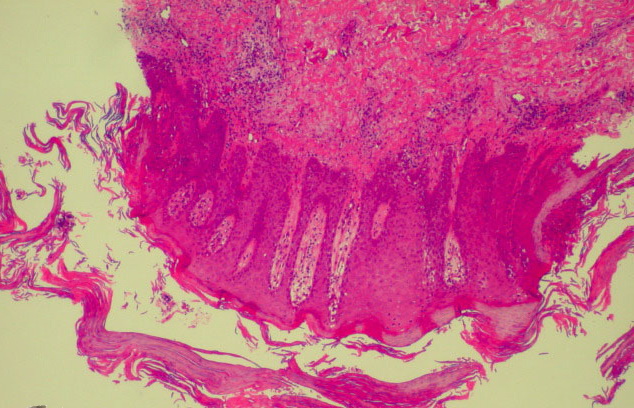

Histopathology Whereas in ordinary psoriasis the spongiform pustule of Kogoj is a very small micropustule and is seen only in early, active lesions, it occurs as a macropustule in all variants of generalized pustular psoriasis and represents their characteristic histologic lesion. The spongiform pustule forms through the migration of neutrophils from the papillary dermal capillaries to the upper layer of epidermis, where they aggregate within the interstices of a spongelike network formed by degenerated and thinned epidermal cells . As the size of the pustule increases, the epidermal cells in the center of the pustule undergo complete cytolysis so that a large single cavity forms . At the periphery of the pustule, however, the network of thinned epidermal cells persists for a much longer time. As the neutrophils of the spongiform pustule move up into the cornified layer, they become pyknotic and assume the appearance of a large Munro abscess . |

In addition to the large spongiform pustules, the epidermal changes in generalized pustular psoriasis are very much like those seen in psoriasis vulgaris, consisting of parakeratosis and elongation of the rete ridges. The upper dermis contains an infiltrate of lymphocytes, and neutrophils can often be seen migrating from the capillaries in the papillae into the epidermis . The oral lesions show the same spongiform pustule formation as those seen on the skin . In the healing stage, the lesions of all types of generalized pustular psoriasis may present the same histologic appearance as ordinary psoriasis . |